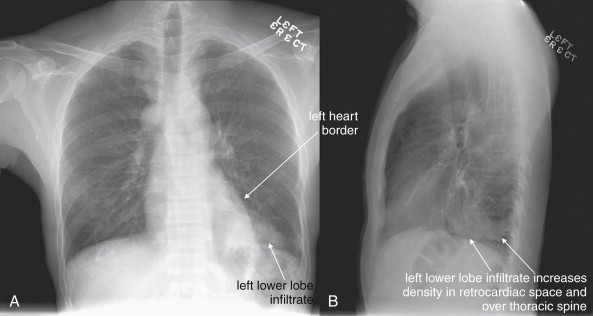

Lateral Upright Chest X-ray View: Retrosternal Space, Retrocardiac Space, and the Spine Sign

The lateral chest x-ray provides important diagnostic information. Unfortunately, this view is usually not obtained when a portable x-ray examination is performed—another good reason to send the patient to the radiology suite for imaging if the clinical condition permits this. The lateral view (Figure 5-16 ) reveals the retrosternal space, which overlies the heart and mediastinum on a frontal projection. This space is usually quite lucent (black) because of the presence of a low-density epicardial fat pad and sometimes lung segments—but when occupied by a soft-tissue mass, this space may appear radiodense (white) (Figure 5-17 ). The lateral chest x-ray also reveals the retrocardiac space. This space normally should be quite lucent (black) (see Figure 5-16). Lower lobe pneumonias may be evident on the lateral view as an abnormally dense retrocardiac region (Figure 5-18 ). On the lateral view, the diaphragms usually form smooth curves descending from anterior to posterior. The space above the diaphragms is usually lucent (black), as it contains low-density lung tissue. Pleural effusions may be evident on lateral view as dense (white) layering opacities replacing the normal curve of the diaphragm in this space (see Figure 5-9). Sometimes pleural effusions form a meniscus against the posterior wall of the thorax, actually reversing the normal curve of the diaphragm. In addition, air beneath the diaphragm (pneumoperitoneum) may be visible on the lateral view (see Figure 5-14).

Figure 5-18.

The spine sign.

The abnormal lateral chest x-ray shows loss of the normal progressive lucency of the thoracic spine as it approaches the diaphragm, called the spine sign. In addition, the retrocardiac space may be less lucent than normal, and the posterior diaphragmatic recess may appear shallow or less lucent than usual, indicating pleural effusion or infiltrate. A, A schematic representation. B, A patient with a retrocardiac infiltrate, illustrating a pathologic spine sign.

The thoracic spine also is visible on a lateral chest x-ray. The normal appearance of the spine is a gradually more lucent (blacker) appearance moving from cephalad to caudad (see Figure 5-16). This is not a result of decreasing spinal density but rather is a normal artifact of the examination technique. When this progressively more lucent appearance is lost, it implies the presence of an abnormal density in the retrocardiac space. This is called the spine sign and is a pathologic abnormality that can be a clue to disease. Remember that the increasing density has a differential diagnosis, including infectious infiltrate, pulmonary edema, pleural effusion, mass, and atelectasis. Other radiographic findings and the patient’s clinical presentation must be used to sort through this differential diagnosis, and additional imaging may be necessary. Nonetheless, this finding can confirm a pneumonia not seen on the frontal projection x-ray. The lateral x-ray is often neglected but is a key additional view that should be obtained whenever possible and carefully reviewed.